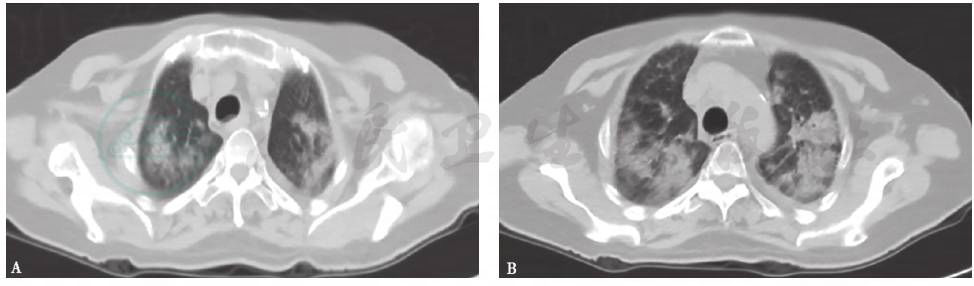

胸部CT:双肺弥漫间质性病变伴多发小结节(图1)。2个月后,随着病程延长,原有结节样病灶增多,病灶融合,形成磨玻璃及实变影,并出现双侧胸腔积液和少量心包积液(图2)。

图1 胸部CT表现(2014-03-05)

图2 胸部CT表现(2014-05-22)

4.胸部影像学表现由双肺弥漫性磨玻璃影并多发小结节样改变,逐渐进展至大片磨玻璃影、局部实变结节并双侧胸腔积液。